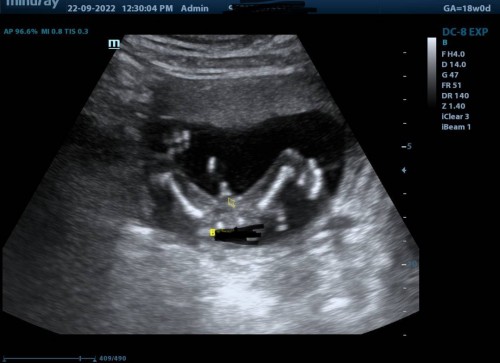

Gender Scan

Hi. Saya scan masa 18w. First time mommy to be. Confirm ke ni baby boy? 😅😂 ada possibility tak jd girl? Haha

Comel jeee terkangkang gitu, betul showoff dia punya hahaha! Tu memang boy sis, saya punya scan semalam girl garis lurus je doctor kata burger kak long 😂

kalau tengok mmg kompem nampak boy.. tapi ada jugak baca kat fb.. dah scan detail, 5d lagi.. smua nampaknya boy.. keluarnya girl.. 😂

Ketara sangat tu dia tunjuk, confirm boy. Sama mcm saya punya baby pun posisi masa scan last week 😂

Biasanya memang tak tukar dah kalau jelas tunjuk boy gitu 😁